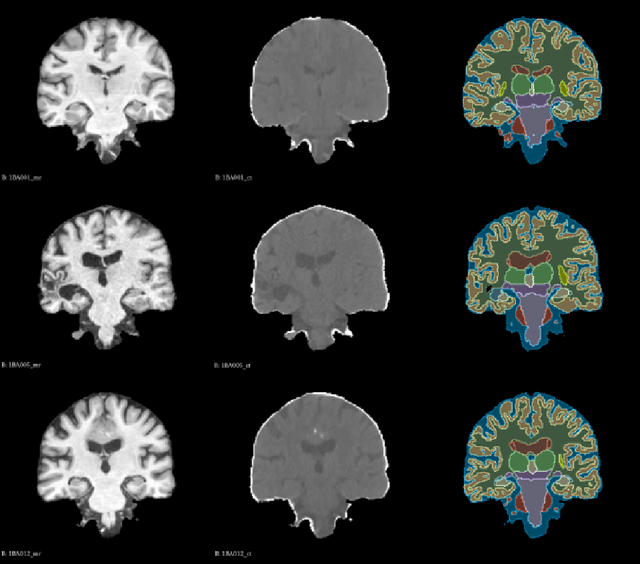

Deformable image registration is an essential approach for medical image analysis.This paper introduces MambaMorph, an innovative multi-modality deformable registration network, specifically designed for Magnetic Resonance (MR) and Computed Tomography (CT) image alignment. MambaMorph stands out with its Mamba-based registration module and a contrastive feature learning approach, addressing the prevalent challenges in multi-modality registration. The network leverages Mamba blocks for efficient long-range modeling and high-dimensional data processing, coupled with a feature extractor that learns fine-grained features for enhanced registration accuracy. Experimental results showcase MambaMorph's superior performance over existing methods in MR-CT registration, underlining its potential in clinical applications. This work underscores the significance of feature learning in multi-modality registration and positions MambaMorph as a trailblazing solution in this field. The code for MambaMorph is available at: https://github.com/Guo-Stone/MambaMorph.